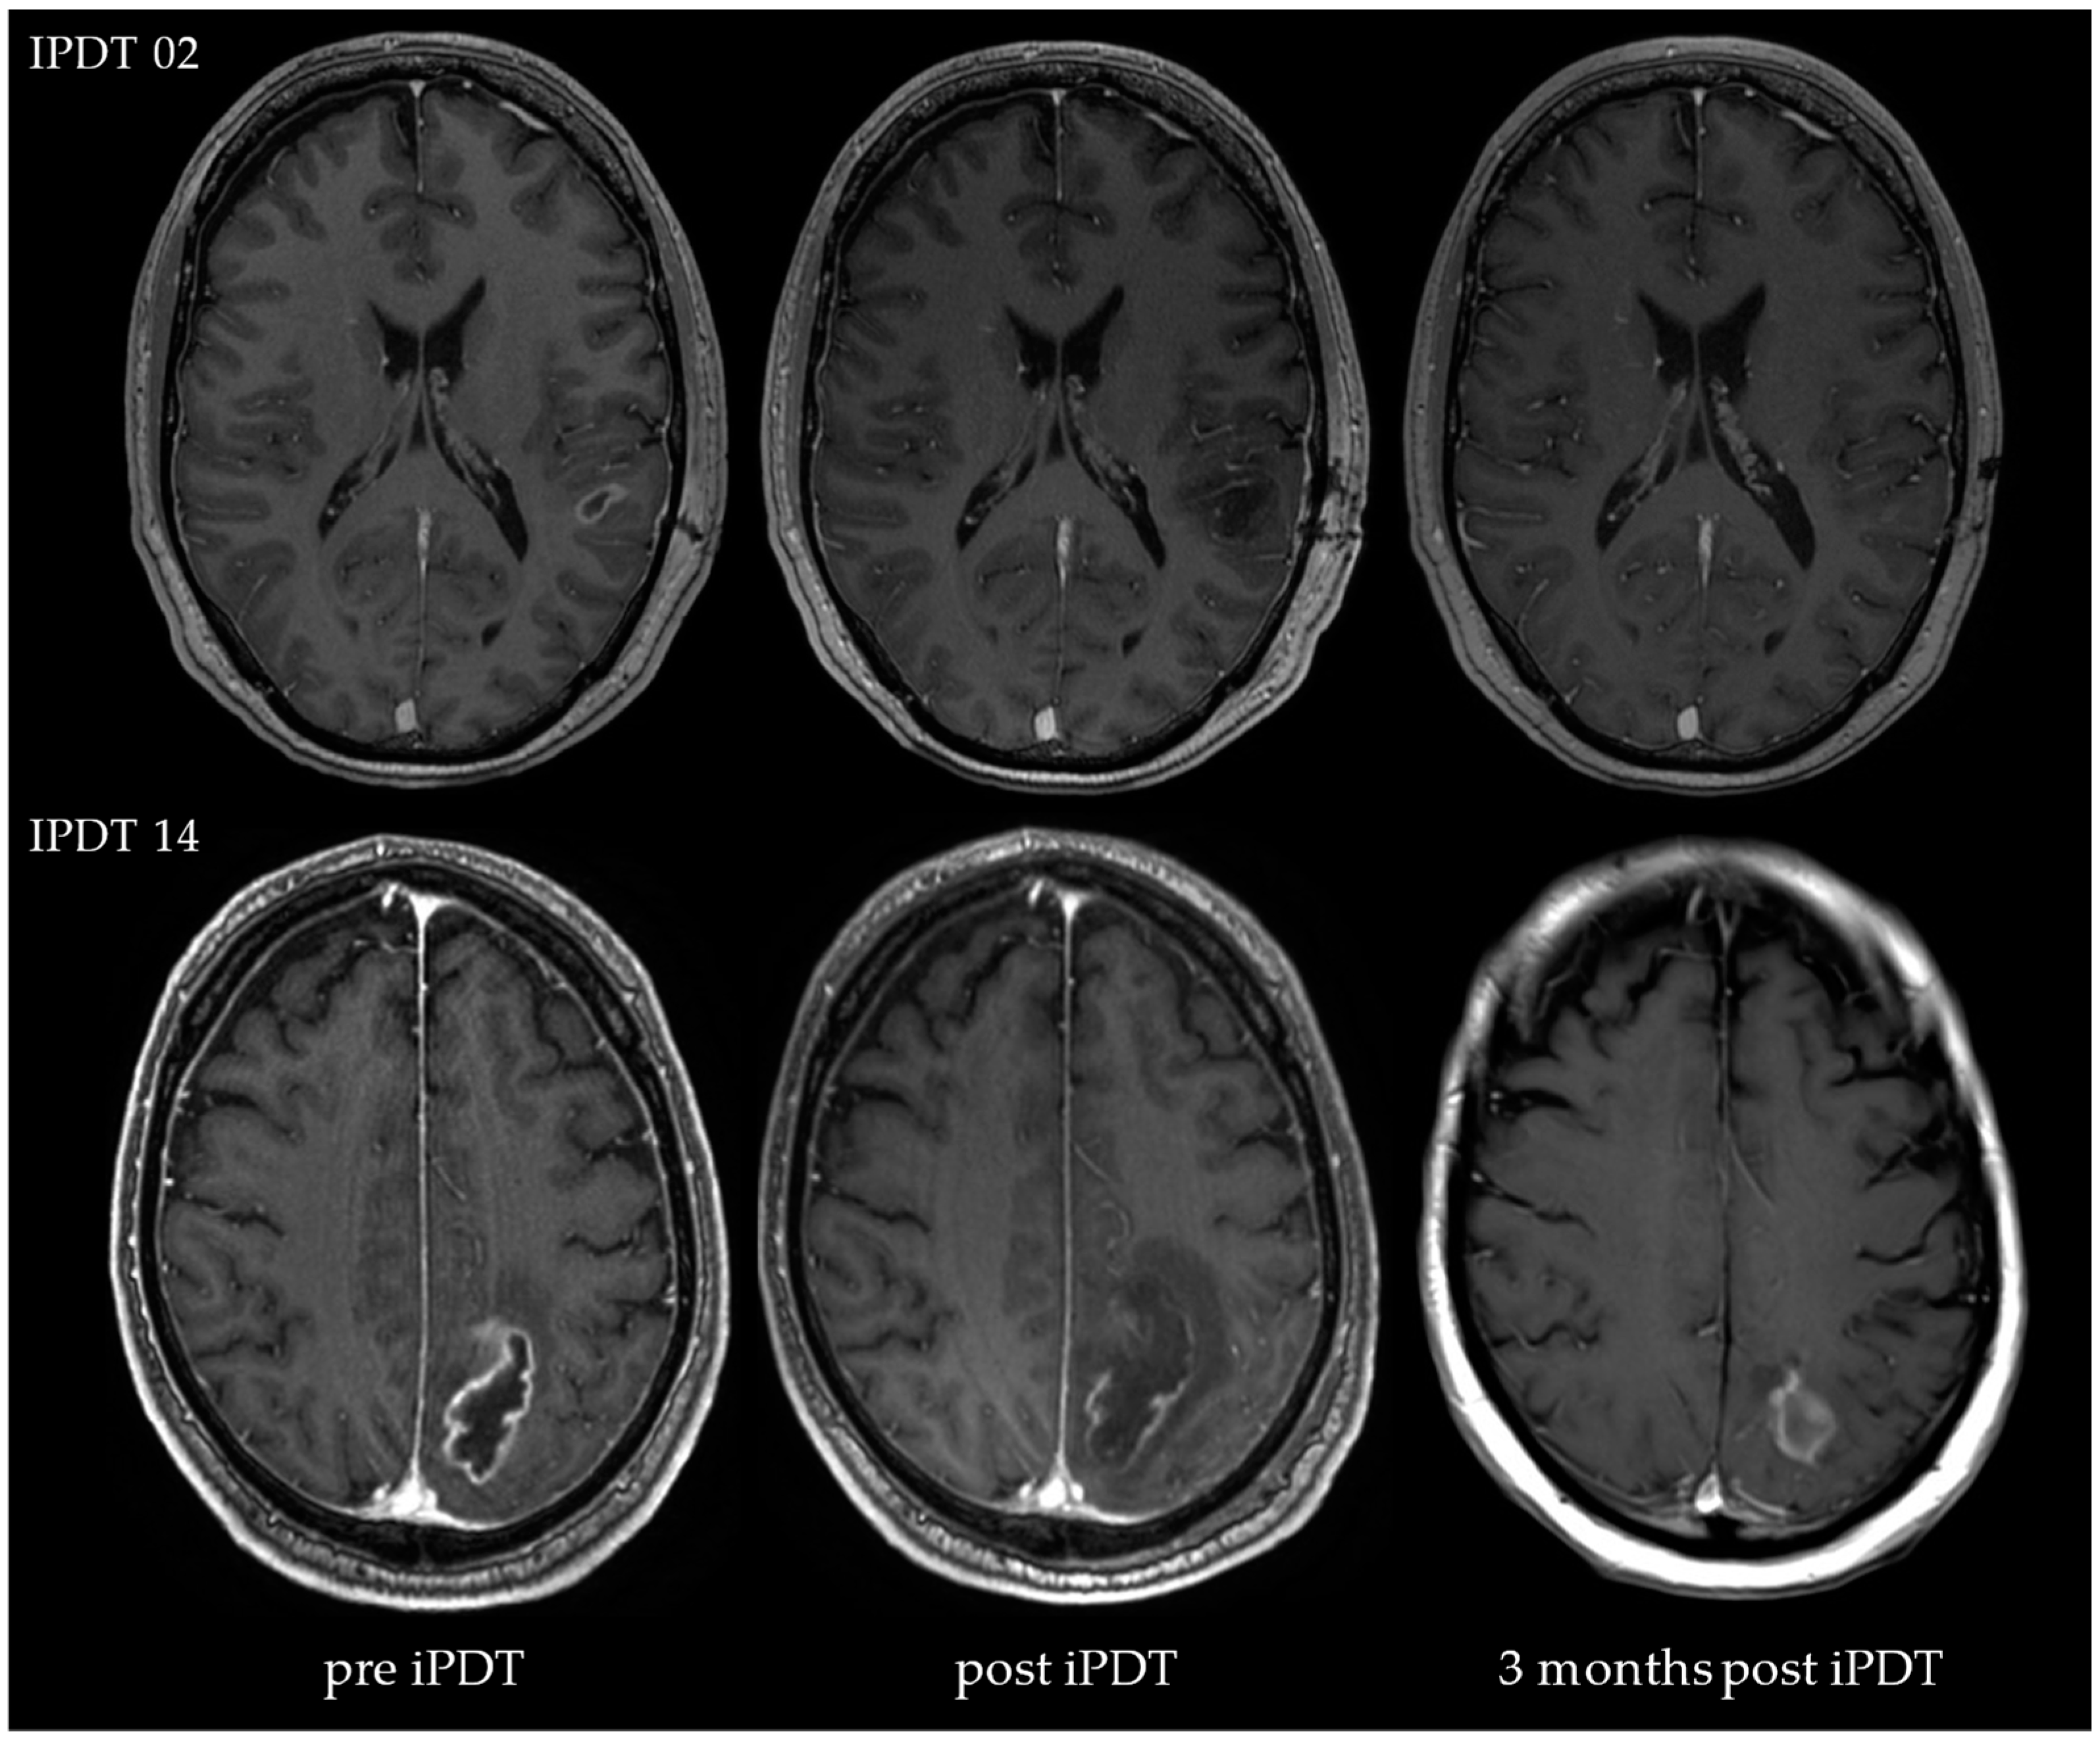

3.2. Volumetric Assessments

4.2. Posttreatment CE

4.3. iPDT Remnant

- The assessment of MRI data showed peculiarities compared to the SOC treatment. In the case of residual or increasing CE after iPDT, advanced imaging techniques (e.g., DWI, MR perfusion and spectroscopy, PET) should be considered to enable better differentiation between vital tumor reactions and tissue reactions/pseudoprogression.